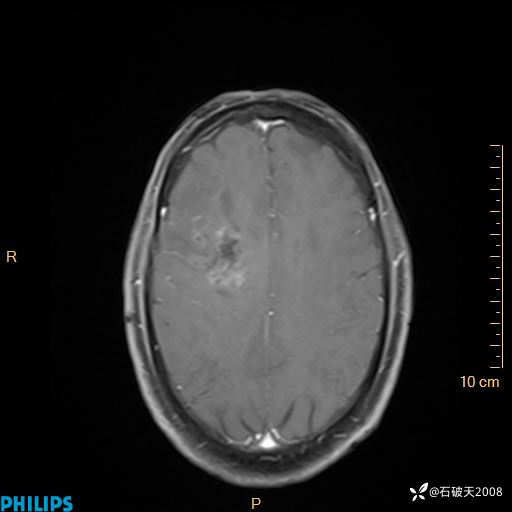

2024.2.21MR

增强轴位